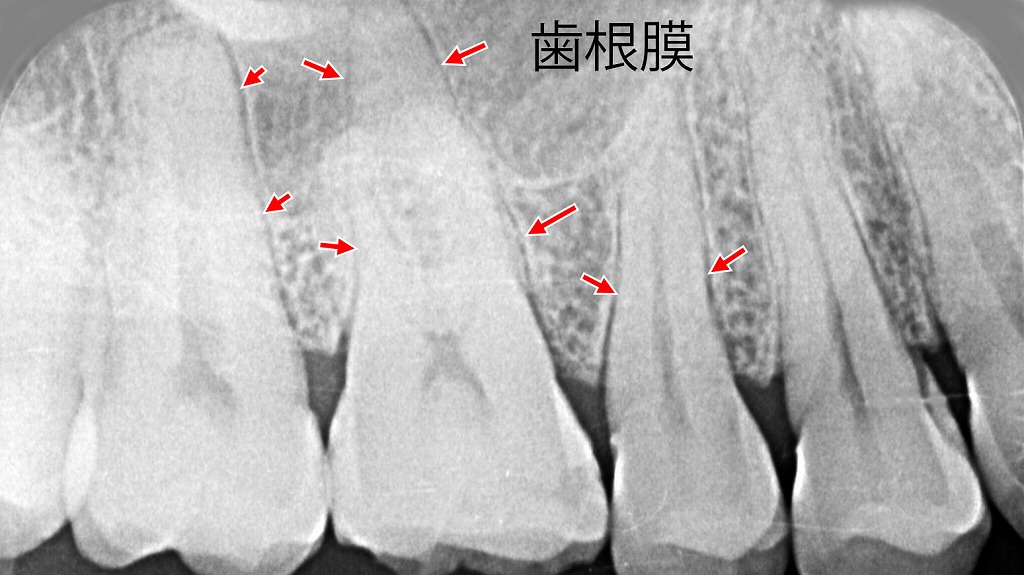

歯根膜|クッションの役割

歯と骨の間にあり、噛む力を分散しショックを吸収します。